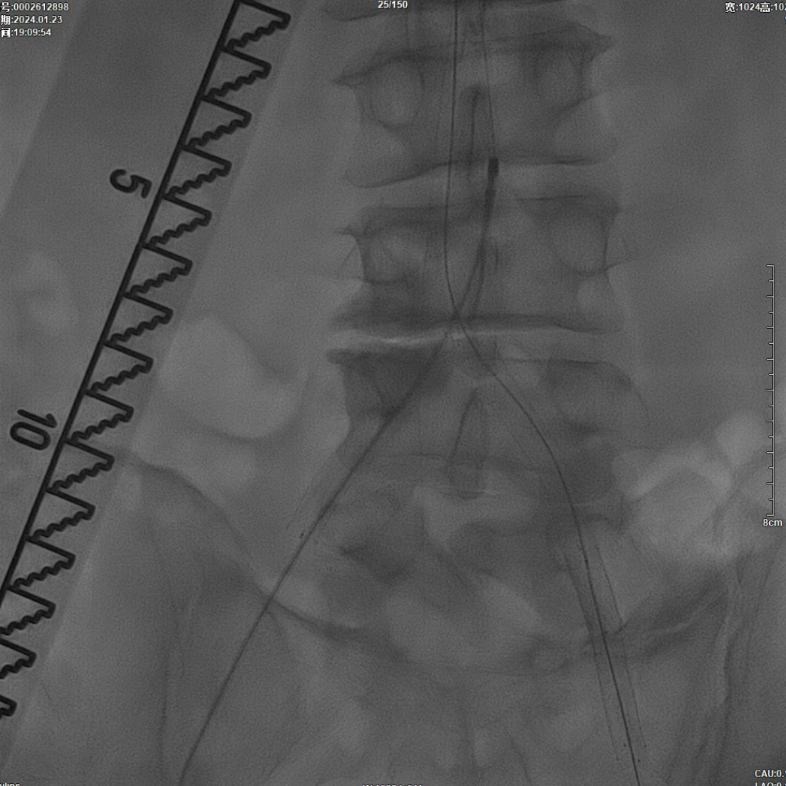

采用8F Rotarex导管对双侧髂动脉及腹主动脉下段进行减容处理。该器械对于陈旧性血栓具有良好的清除效果,且适用于支架内病变的治疗。减容治疗的主要目的在于获得理想的管腔空间,同时降低远端动脉栓塞的风险。

减容治疗